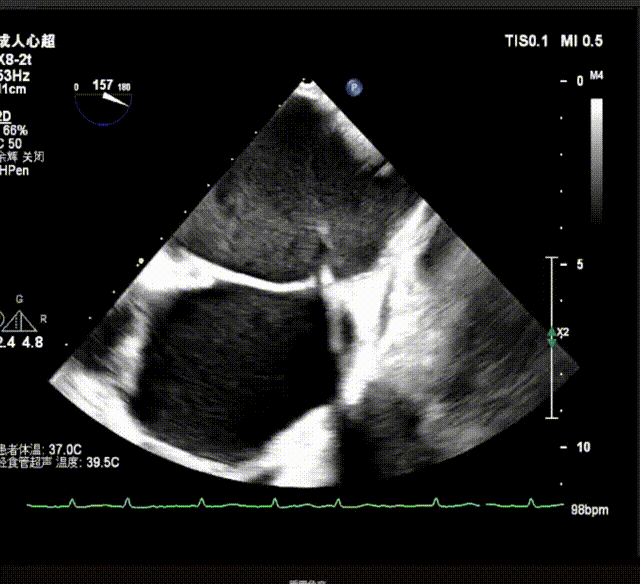

术前超声诊断:双房扩大,二三尖瓣中度关闭不全,二尖瓣P2P3偏P2区脱垂,主动脉瓣轻中度关闭不全,升主动脉增宽,TEER解剖难度分级:黄区,轻度肺高压。LVEF为73%。

术前超声诊断

X-plane视窗可见二尖瓣病变区脱垂,重度偏心性返流.

3D enface view示二尖瓣P2P3区瓣叶脱垂,偏心性返流